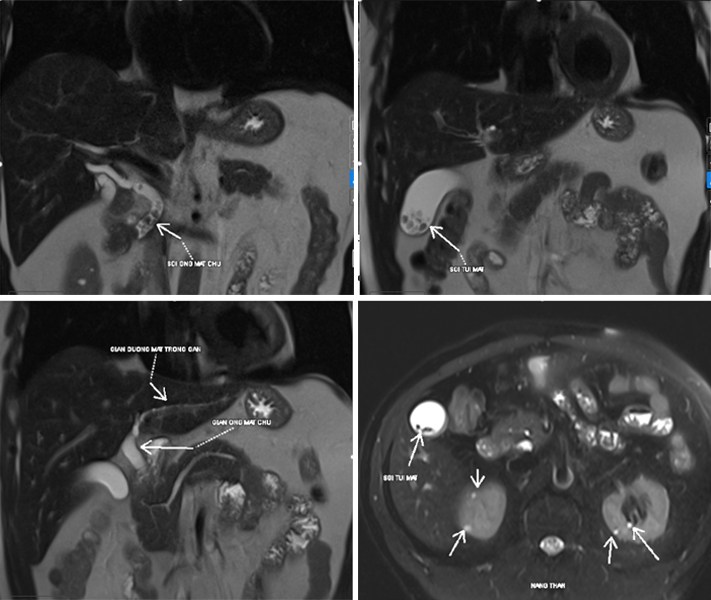

TTƯT.TS.BS Vũ Trường Khanh, Trưởng khoa Khoa Tiêu hóa – Gan mật – Tụy, Bệnh viện Đa khoa Tâm Anh Hà Nội cho biết, kết quả thăm dò chuyên sâu cho thấy ông Đông bị giãn nhẹ đường mật trong gan hai bên. Đặc biệt, ống mật chủ giãn, đường kính có đoạn lên tới 9 mm, bên trong có nhiều sỏi nhỏ tập trung thành đám dài tới 31 mm. Ngoài ra, túi mật cũng chứa nhiều sỏi kích thước lớn (23×21 mm). Sỏi trong ống mật chủ và tình trạng giãn đường mật nếu không được xử lý kịp thời có thể gây ứ mật kéo dài, dẫn đến viêm đường mật cấp, nhiễm trùng huyết, viêm tụy cấp, thậm chí đe dọa tính mạng.

Đầu tháng 5, gia đình đưa ông đến Bệnh viện Đa khoa Tâm Anh Hà Nội để khám chuyên sâu. Tại đây, sau khi khám lâm sàng và khai thác kỹ bệnh sử, bác sĩ nghi ngờ nguyên nhân không đơn thuần từ dạ dày hay đại tràng như các kết luận trước đó. Ông Đông được chỉ định thực hiện các xét nghiệm máu và chụp cộng hưởng từ ổ bụng (MRI) nhằm đánh giá toàn diện hệ gan mật.